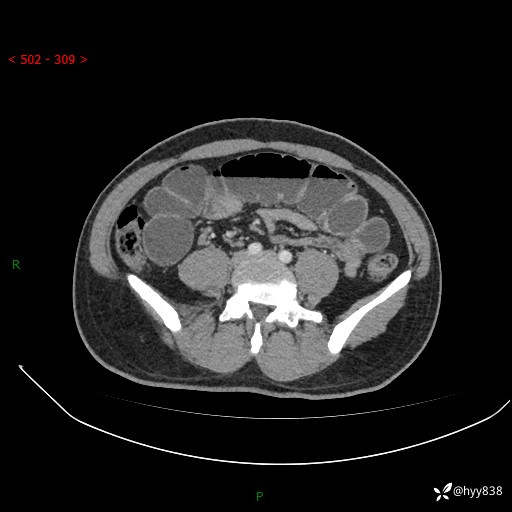

年轻男性,腹痛5月余。除了肠梗阻,你还能看到什么---结果公布~

主诉:腹痛5月余。

现病史:患者于5月前无明显诱因开始出现腹痛,上明显,为间断性胀痛不适,无畏寒发热,无心慌气促等特殊不适,遂来我院。我院门诊遂以“腹痛原因待查”收入我科。 起病以来,患者精神、饮食、睡眠欠佳,大小便正常。体力体重无明显变化。

腹部CT增强扫描(动脉期+静脉期)